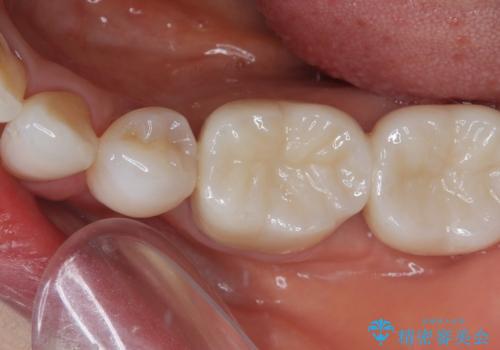

奥歯の目立つ銀歯をセラミックに オールセラミッククラウン治療

- 奥歯の目立つ銀歯と、神経が失活して変色した前歯を気にして来院された患者様です。

銀歯と歯の間に隙間があり、冷たいものがしみる知覚過敏の症状が認められたため、銀歯を白くするだけでなく、知覚過敏症状の改善も狙って補綴治療を行うこととしました。

長年口を開ける度に気になっていた銀歯が一気に自然な色合いとなり、患者様には大変満足していただけました。